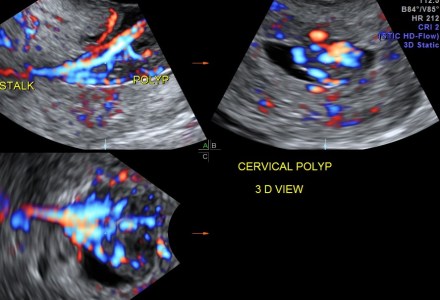

ENDOMETRIAL POLYP WITH A STALK PRESENTING IN THE CERVIX